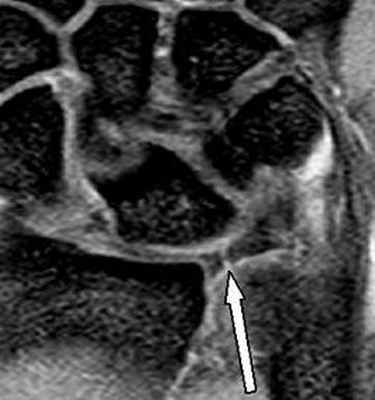

(Слева) МР-артрография в режиме Т1ВИ FS, коронарный срез: определяется разрыв тыльной части ЛПС. Контрастный препарат через дефект распространяется в среднезапястный сустав. Также отмечается разрыв треугольного фиброзно-хрящевого комплекса (ТФХК), вследствие ко торого контрастный препарат поступает в дистальный лучелоктевой сустав.

(Справа) МР-артрография в режиме Т1ВИ FS, коронарный срез, этот же пациент: определяются разрывы мембранозной части ЛПС и мембранозной части треугольного фиброзно-хрящевого диска. (Слева) МР-артрография в режиме Т1ВИ FS, аксиальный срез: визуализируется интактный тыльный пучок, ладонный пучок поврежден. Следует отметить расширение суставной щели, истончение хряща и кисто-зоподобную перестройку.

(Справа) МР-артрография в режиме Т1ВИ FS, коронарный срез: определяется консолидированный перелом дистального отдела лучевой кости. Конгруэнтность суставных поверхностей нарушена. В ладьевидно-полулунном промежутке видна рубцовая ткань. Отмечается распространение контраста в среднезапястный сустав, что, вероятно, обусловлено рубцеванием или сбросом контрастного препарата из лучезапястного сустава в дистальный лучелоктевой сустав через дефекте ТФХК. (Слева) Артрография, заднепередняя проекция, кисть отклонена в локтевую сторону: визуализируется увеличение ладьевидно-полулунного промежутка, однако контрастный препарат в среднезапястный сустав не поступает.

(Справа) МР-артрография в режиме Т1ВИ FS, коронарный срез, этот же пациент: отмечается, что ладьевидно-полулунная связка интактна. Выявленные изменения свидетельствуют о ее заживлении после разрыва.

• Распространение контрастного препарата через разорванную связку; часто визуализируется культя связки

• Оценка ладонной, средней и тыльной порций выполняется отдельно; повреждение каждой порции следует отмечать в протоколе описания

• Вдоль расположенных друг против друга краев ладьевидной и полулунной костей часто выявляется отек костного мозга

• Может наблюдаться тыльный подвывих ладьевидной кости относительно лучевой кости

(Слева) МР-артрография в режиме Т1ВИ, коронарный срез: визуализируется крупный дефект ЛПС. Суставная щель расширена. Следует отметить наличиедегенеративных перфораций в центральной части ТФХК.

(Справа) МР-артрография в режиме Т2ВИ FS, коронарный срез: визуализируется крупный дефект ЛПС. Суставная щель расширена. Следует отметить неравномерное истончение хряща и кистозные изменения суставных поверхностей, обусловленные нестабильностью. Это говорит о том, что разрыв данной связки был биомеханически значим. (Слева) Артрография в заднепередней проекции: распространение контрастного препарата через дефект ЛПС в среднезапястный сустав. ПТС интактна.

(Справа) МР-артрография в режиме Т1ВИ, коронарный срез, этот же пациент: визуализируется интактный тыльный пучок ЛПС. Разрыв мембранозной порции на данном срезе не виден (располагается кпереди). Разрыв центральной мембранозной порции ЛПС часто протекает бессимптомно. (Слева) Непрямая МР-артрография в режиме Т1ВИ FS с КУ, коронарный срез: визуализируется значительное расширение ладьевидно-полулунного промежутка. Отмечаются признаки артрита лучеладьевидного сустава. Головчатая кость смещена проксимально в промежуток между ладьевидной и полулунной костями. Картина характерна для ПЛПК запястья.

(Справа) МР-артрография в режиме PD FS, сагиттальный срез, этот же пациент: определяется разрыв восстановленного фрагмента связки, имеющего аморфную структуру и неровный контур. Полулунная кость отклонена в тыльную сторону, что позволяет заподозрить ТНПС. Положение полулунной кости должно быть сопоставлено с осью ладьевидной кости на соседних срезах.